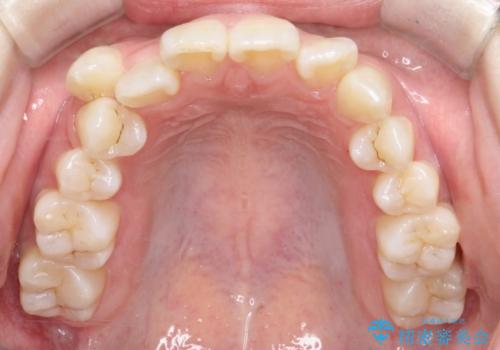

- 患者様は下顎の前歯が3本しかないという特異な歯列を持ち、噛み合わせのバランスが崩れていました。上下の歯の本数が通常と異なるため、抜歯部位の選定が重要となるケースでした。診査の結果、歯の位置や咬合のバランスを考慮し、上顎の両側小臼歯2本と左下の小臼歯1本を抜歯することで、上下の噛み合わせを整える方針としました。矯正装置は、**目立ちにくいハーフリンガル(上顎は裏側矯正・下顎は表側矯正)**を採用しました。

まず、計画通りに抜歯を行い、歯列のスペースを確保しました。上顎は裏側矯正(リンガル)で目立たないように配慮しながら歯を後方へ移動し、下顎は表側矯正を使用して、3本の前歯の位置関係を調整。上下の歯の噛み合わせを細かくコントロールしながら、全体のバランスを整えました。治療後は「歯並びがきれいになり、噛み合わせもしっかり合うようになった」と患者様にも満足していただけました。